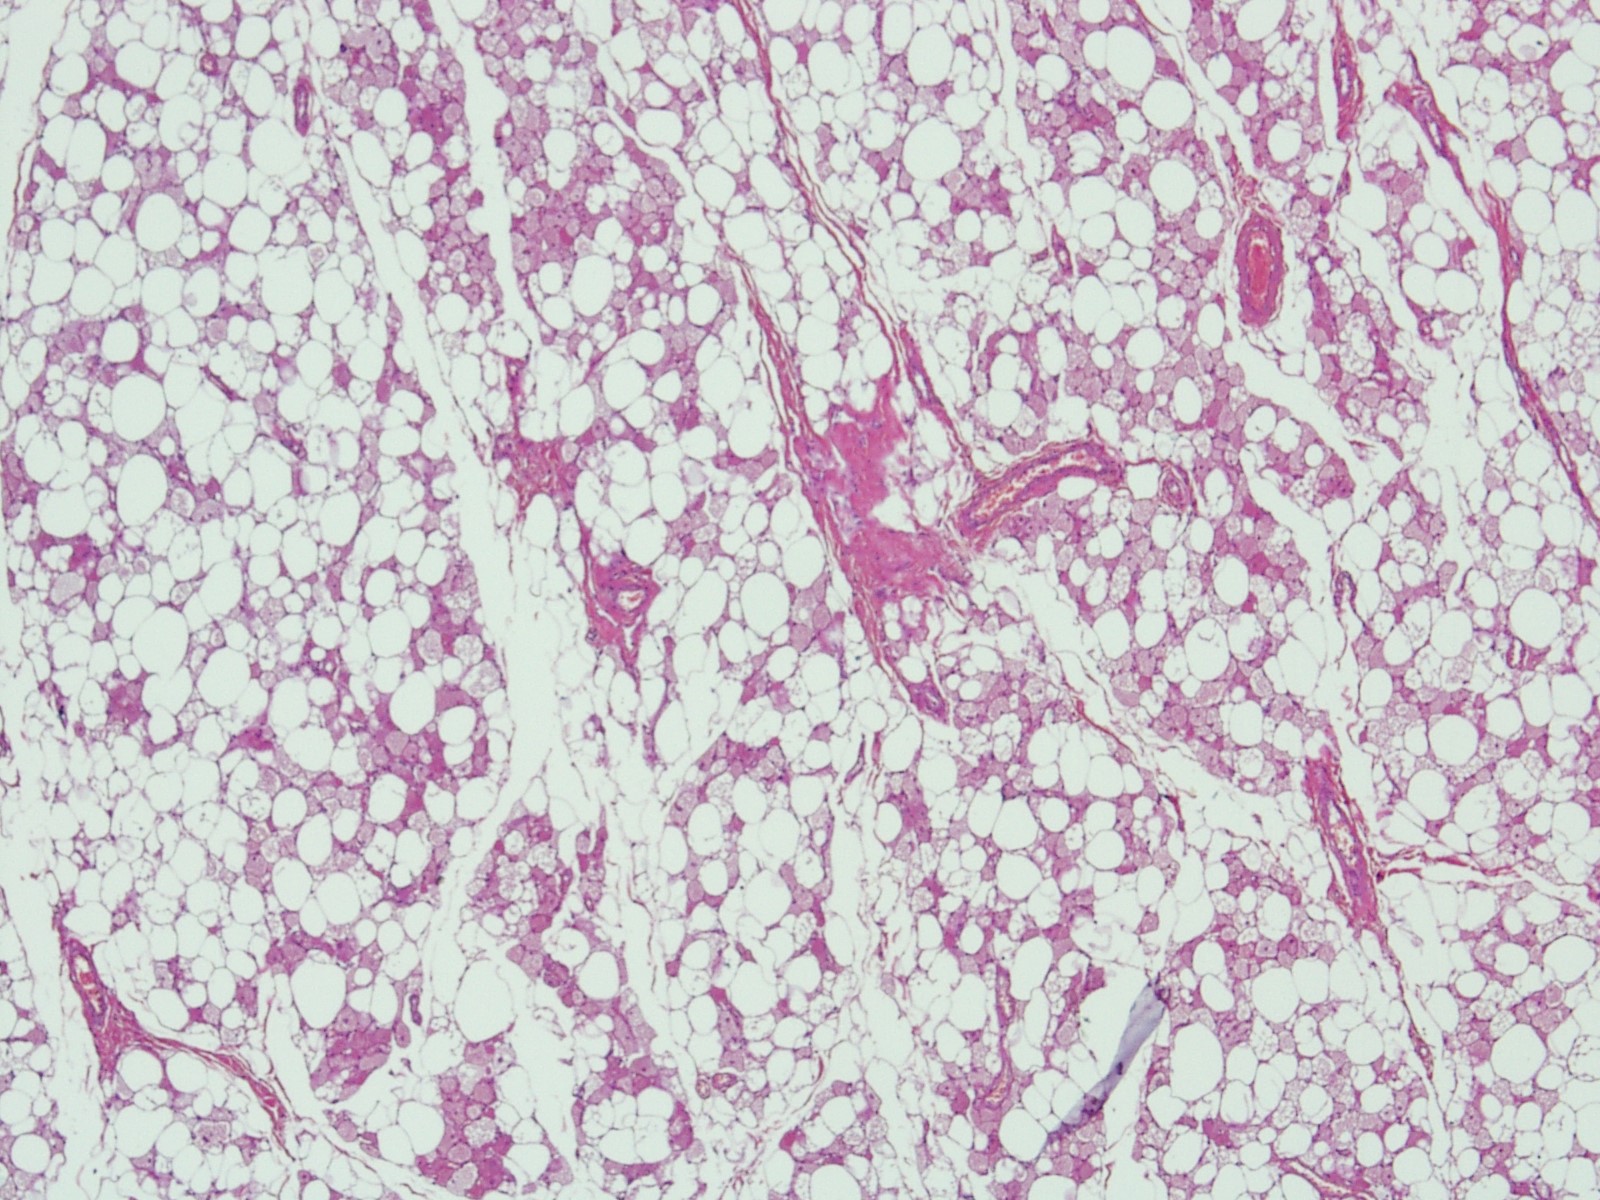

Microscopic (histologic) description

- Neoplastic lesion composed of polygonal brown fat cells with stromal cells in the background (Case Rep Oncol 2017;10:438)

- Large number of pale and eosinophilic brown fat cells with multivacuolated, eosinophilic granular cytoplasm and small central nucleus (about 70%) admixed with variable amount of univacuolated white cells (Case Rep Oncol 2017;10:438, Am J Case Rep 2020;21:e921447, J Comput Assist Tomogr 2019;43:793, J Pathol Transl Med 2017;51:499, Am J Surg Pathol 2018;42:951, Virchows Arch 2021;478:527)

- Multivacuolations resemble lipoblasts

- Morphological variations or subtypes: typical, myxoid (9%), lipoma-like (7%), spindle cell (2%), thick bundles of collagen fibers, presence of mast cells and exclusively containing brown fat cells (Case Rep Oncol 2017;10:438, Am J Case Rep 2020;21:e921447, Virchows Arch 2021;478:527)

- Cytological atypia, necrosis and mitosis is unusual (J Pathol Transl Med 2017;51:499, Am J Surg Pathol 2018;42:951, BMC Surg 2021;21:30)

Microscopic (histologic) images